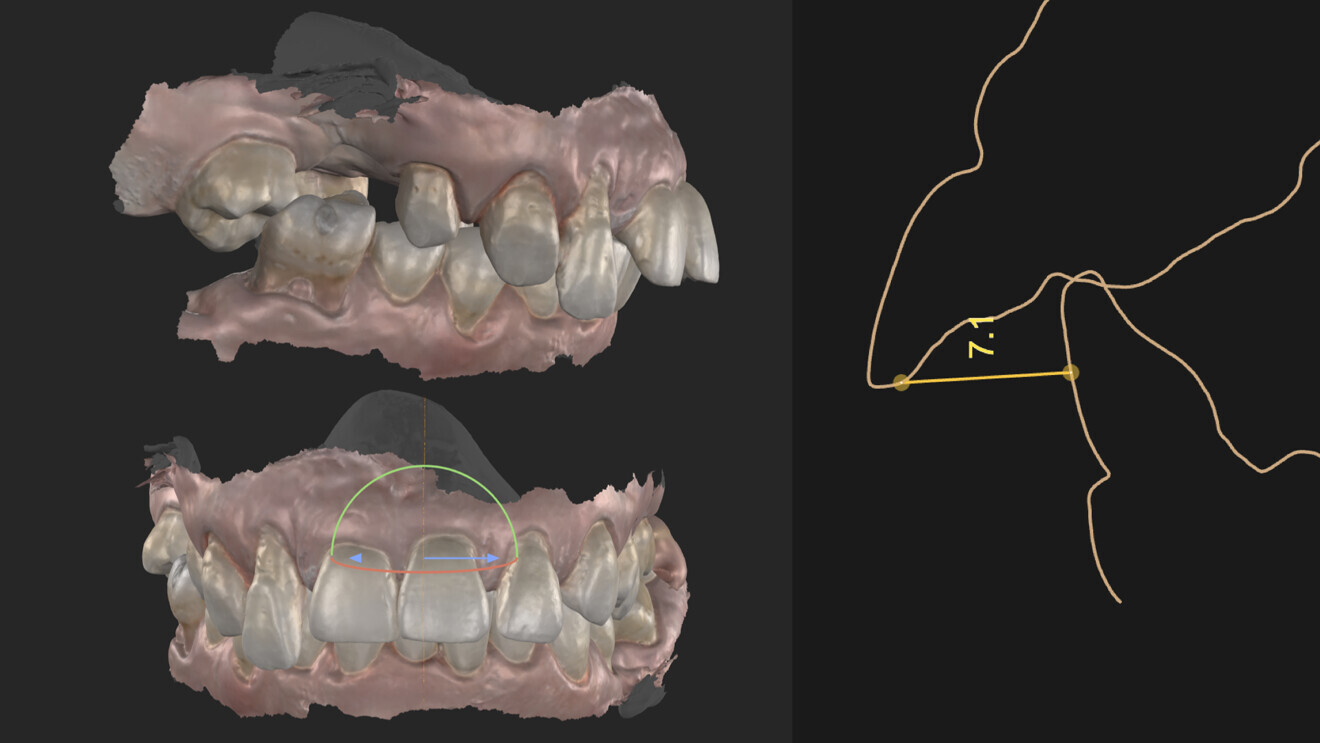

Fig. 3: Overjet and overbite.

From analysis of the patient’s documentation, it was clear that loss of bony support had caused her teeth to migrate and tilt forwards such that they extended over the lower lip, resulting in excessive overjet. Additionally, there was a noticeable deviation of the midline, which had shifted towards the right. The incisal edges no longer followed the natural contour of her lower lip during a smile.

From an occlusal perspective, the patient exhibited both an excessive overjet and overbite (Fig. 3). However, her gingival architecture remained largely intact. Despite the presence of deep, untreatable periodontal pockets, there was minimal recession, thanks to her thick periodontal biotype (Fig. 4). This offered us an advantage. With careful planning and proper design, we were confident that we could preserve and slightly modify her gingival tissue to meet her aesthetic goals.

We begin with facial analysis and use planning software to select the appropriate tooth forms that complement the patient’s facial structure and determine the optimal apico-coronal tooth positioning. This step is particularly beneficial when the software allows us to modify tooth forms in relation to the patient’s soft-tissue contours, including papillary height, ideal gingival zeniths and other critical aesthetic parameters (Fig. 5). For this patient, as we aimed to achieve high papillae and have an excess of soft tissue to manipulate, we opted for trapezoidal tooth forms or potentially triangular forms rather than square ones. Once the desired tooth forms are selected, they are exported to a 3D CAD software program for precise positioning in the buccolingual dimension.

Fig. 6: Combination of the CBCT and the intra-oral scans for segmentation.